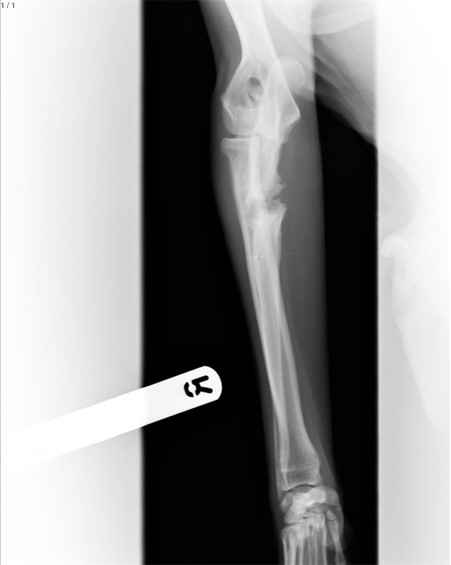

The following is my understanding of how our vet described the condition. The elbow is the joint where the humerus, the upper bone of the front leg, meets the radius and ulna, the two bones that form the lower leg. Elbow dysplasia is where the bones within the elbow joint fail to develop properly. Part of the elbow consists of a lump of bone, the “anconeal process”, fused to the end on the ulna, that help the elbow joint articulate, or bend. In some elbow dysplasia conditions this lump of bone does not fuse to the ulna, remaining “ununited”, the technical term being UAP – “Ununited Anconeal Process”. In Sam’s case, and I believe in many cases, the lump of bone did not fuse to the ulna because the radius grew disproportionately longer than the ulna, preventing the lump of bone from fusing with the ulna.

On 22nd June, 2 months since first noticing Sam’s limp, we met with the original referral vet to discuss the scans and specialist report. In addition to dysplasia, Sam had what the vet described as a “mild” radioulnar step in the front right leg. The two bones of the upper leg were out of alignment, the ulna not seated in the elbow as it should be. He could operate, and given Sam’s young age, the operation had a high chance of success. Sam would be running free within 3-4 months. I would never have thought that being told that my dog needed quite a serious operation would seem like such good news.

This all seemed quite invasive enough, but the vet had not finished. He planned to break Sam’s leg. The ulna would be surgically cut through, allowing muscle to pull the bone back into the correct alignment as the bone healed, so that all bones meet at the elbow as they should. We just had to trust the vet, and so we agreed to the operation for Wednesday 29th June. It is very unsettling to drop off your dog off at the vet to have his leg broken, and we were relieved to get a call that afternoon to confirm that the operation had gone well, even more relieved to collect Sam later in the day. Sam’s journey to recovery had begun.

We had been led to believe that an X-ray two months after the operation should confirm that the cut ulna had healed, and Sam would be allowed some off lead exercise. Once again, the vet had been over optimistic. The incision was healing, but not healed. Once again, we were disappointed and frustrated; the end of the road remained far over the horizon.